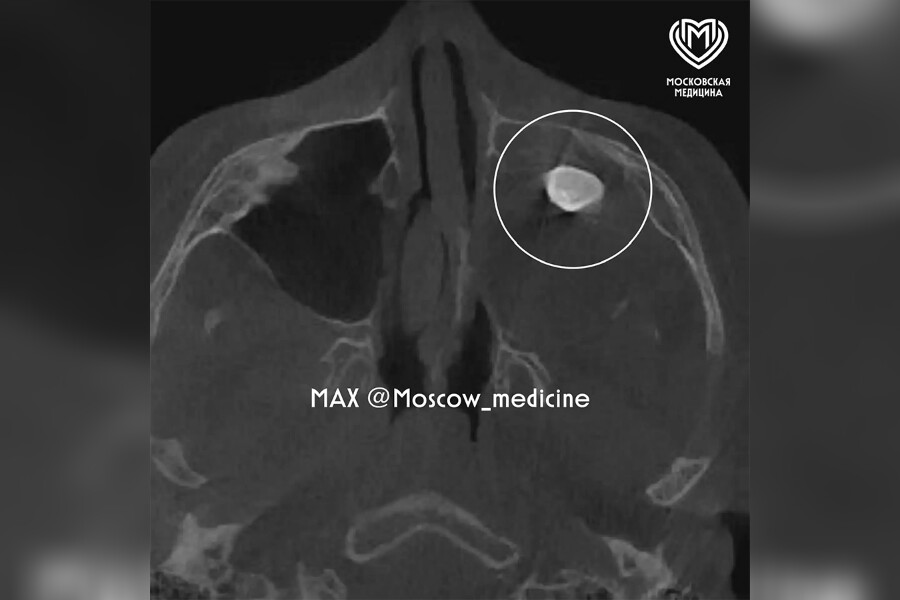

Уточняется, что мальчику нужно было провести операцию по Колдуэлу Люку, то есть, обеспечить доступ через верхнюю десну, чтобы вернуть ему возможность нормально дышать. Сделав разрез, врачи обнаружили новообразование, внутри которого и находился зуб.

«Новообразование отправили на исследование и выяснили, что это тератома – эмбрионально-клеточное новообразование, внутри которого могут находиться элементы тканей, несвойственные этому участку тела: волосы, ногти, мышечные волокна, кости или зубы», – пояснили специалисты.

По словам Вугара Достиева, тератомы очень редко располагаются в зоне лица, чаще в крестцовой области. Ни КТ, ни рентген новообразование не показали, поскольку оно занимало фактически всю левую полость носа.